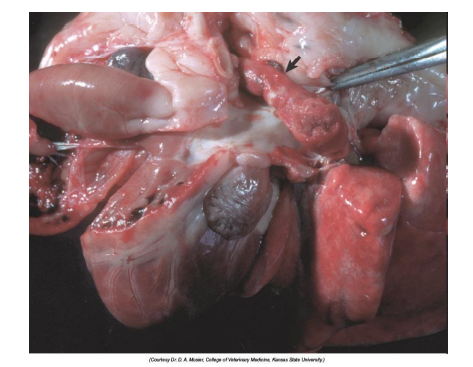

What is this? Give Disease diagnosis and possible cause

Liquefactive necrosis

Diseases dg: polioencephalomalacia

Possible causes – thiamine deficiency, lead toxicosis, etc.